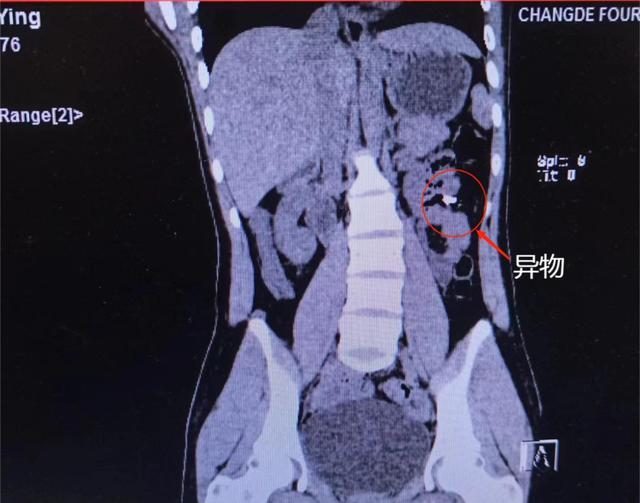

入院后,急诊科医生,为其进一步完善了腹部CT平扫成像检查,发现左肾前方肠管内见两个结节状及片状高密度影,考虑为结肠内异物存留。经过消化内科的专科治疗,患者病情逐渐平稳,腹痛症状明显改善。